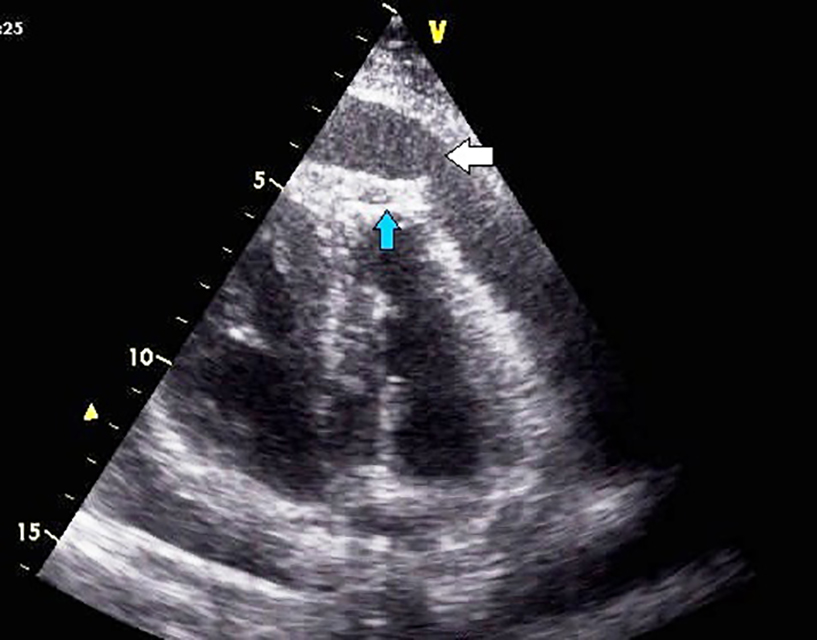

Pericardial effusions are difficult to diagnose, as the clinical examination might be essentially normal in haemodynamically stable patients and tachycardia may be the only sign [1,2]. Cardiomegaly with a flask-shaped heart and clear lung fields on chest X-ray is suggestive of significant pericardial effusion [1,8,10]. ECG may be normal or may show non-specific ST and T-wave abnormalities. Occasionally, low QRS voltage may be seen, but that is more specific for tamponade [1]. Two-dimensional transthoracic echocardiography is the preferred investigation for pericardial effusion as it can determine the size, location, and haemodynamic significance of a pericardial effusion and is also low cost and easily available [1,2,4,13,14]. Upon detection of the effusion, it is imperative to assess the size of the effusion, look for signs of tamponade and any evidence of associated illness [2]. Though echocardiography is fairly conclusive in diagnosing pericardial effusion (Figure 1, Figure 2), computed tomography (CT) or cardiac magnetic resonance (CMR) imaging is useful in providing a wider field, detecting loculated effusion, thickening of the pericardium, and detecting pericardial and myocardial malignant deposits. Cytology of the deposits may be helpful in the differentiation of malignant and non-malignant deposits (pericardial mesothelial cells could resemble malignant cells but could be identified by special stains) and also picks up associated thoracic abnormalities [1,2,12,13,14)

Figure 1. Two-dimensional transthoracic echocardiography of a patient with primary bronchogenic carcinoma, in apical four-chamber view showing pericardial effusion (broad white arrow) and malignant deposits in the left ventricular apex (blue arrow).

115_Soman_Figure 1.jpg